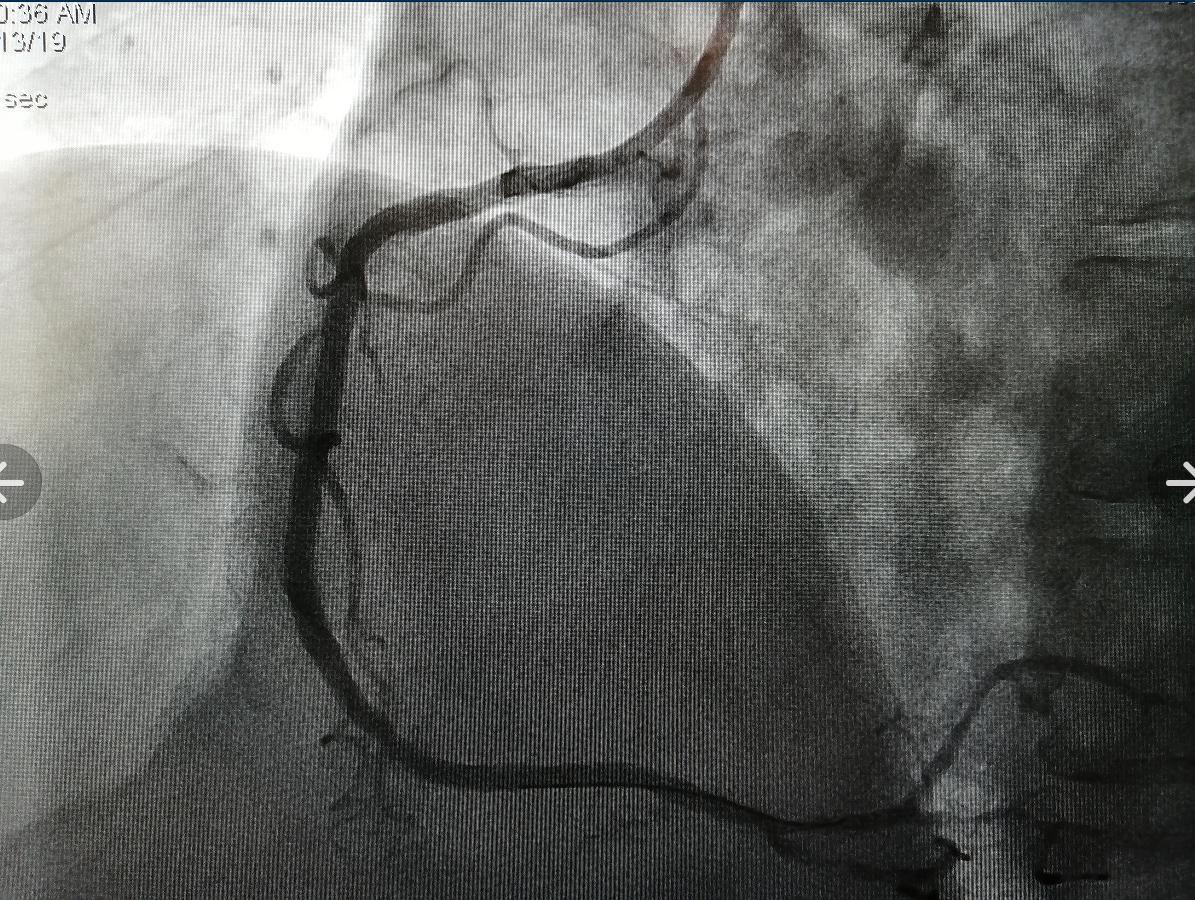

為了進(jìn)一步明確導(dǎo)致患者心衰的“元兇”,使患者得到更為精準(zhǔn)的治療,李慧新主任及楊光醫(yī)生為患者完善了冠脈造影檢查。造影提示:冠脈三支病變(右冠近中段99%狹窄,前降支中段85%狹窄,回旋支遠(yuǎn)段60%狹窄),予以右冠狀動(dòng)脈行支架植入治療。術(shù)后,患者心衰癥狀明顯緩解,胸悶氣喘的癥狀沒(méi)有再出現(xiàn),她和家人均對(duì)治療結(jié)果表示滿意。